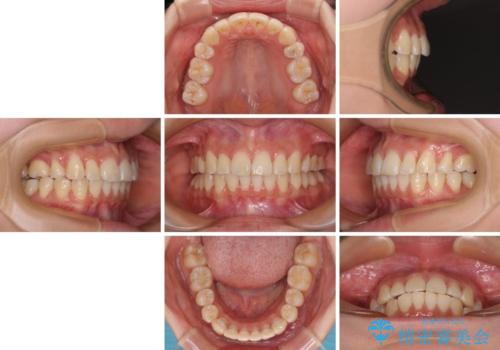

前歯の突出感が改善されるだけでなく、奥歯の咬み合わせも改善され、食いしばりをしにくい状態に仕上げることができました。

- 口を閉じたときに唇の間から飛び出してくる前歯を気にして来院された患者様です。

骨格的に上顎骨が前方位にあるため、左右の第一小臼歯を抜歯し、ワイヤー装置にて咬み合わせを整えていくこととしました。